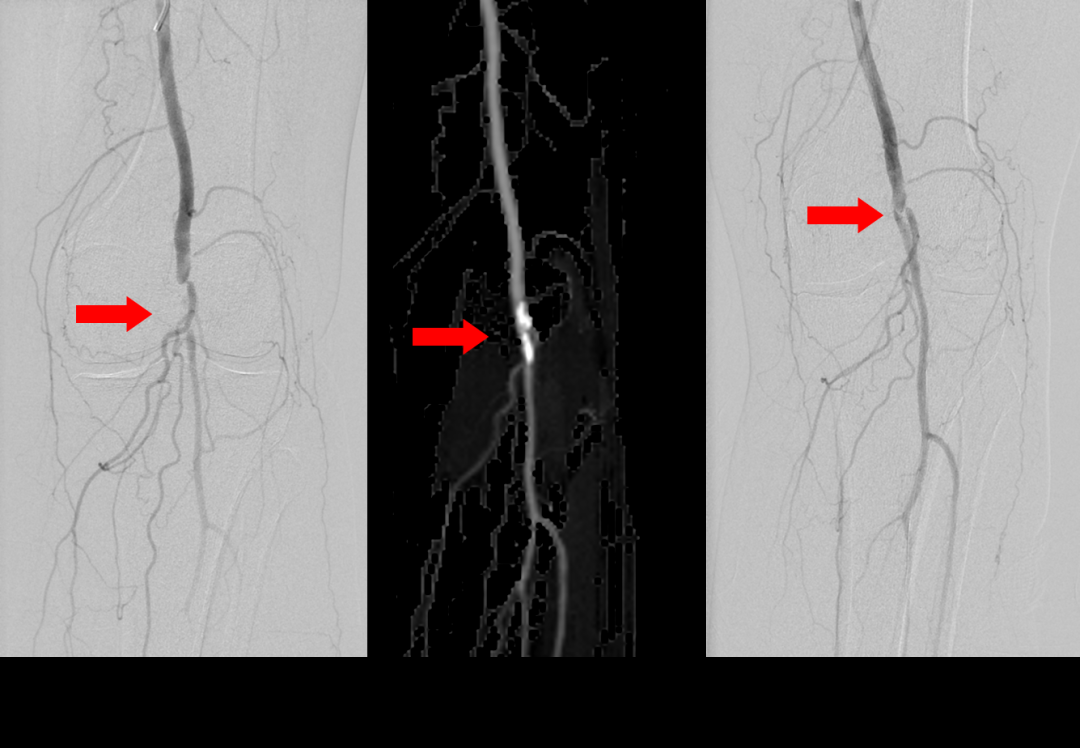

蔡主任首先在局麻下进行血管介入手术,利用球囊扩张,打通阻塞的腘动脉,恢复腿部的血液供应。针对难以愈合的烧伤创面,尚春波医生采用清创+VSD负压引流术。手术结束后,医生小心翼翼地更换了。尚和护士邓彩云为王奶奶穿衣服,直到她康复埃德。

蔡主任首先在局麻下进行血管介入手术,利用球囊扩张,打通阻塞的腘动脉,恢复腿部的血液供应。针对难以愈合的烧伤创面,尚春波医生采用清创+VSD负压引流术。手术结束后,医生小心翼翼地更换了。尚和护士邓彩云为王奶奶穿衣服,直到她康复埃德。